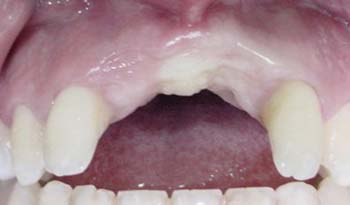

Se presenta un paciente masculino de 21 años de edad, aparentemente sano, no fumador y sin alteraciones sistémicas, atendido en el centro quirúrgico de la Facultad de Odontología de Piracicaba-Unicamp, el cual presentaba deficiencia de reborde alveolar en región anterior del maxilar, siendo la causa de la pérdida de reborde alveolar la atrofia posterior a la extracción de los dientes 11 y 21 (Fig. 1)(Fig. 2). Fué realizada la colocación de un dispositivo de DOA bajo anestesia local (solución de Lidocaína al 2% y epinefrina 1:100.000 IU) y sedación consciente vía oral (Normonid ®- Midazolam). El distractor utilizado fue del tipo yuxtaoseo (Conexión Implant System® - SP-Brasil), con un patrón máximo de distracción de 10 mm según las especificaciones del fabricante. (Fig. 3)

Fig. 1

Imagen preoperatoria donde puede apreciarse la atrofia existente en la región anterior del reborde alveolar.

Clínica y radiográficamente se observó un aumento en altura y espesura del reborde alveolar (Fig. 9 y 10), obteniéndose un aumento óseo de 9 mm (Fig. 11) logrando una óptima estabilidad primaria de los implantes. No hubo evidencia clínica de alteración sensorial o reabsorción a nivel del reborde alveolar. Tanto en los pos-operatorios de la primera y segunda fase quirúrgica no se observaron señales de infección.

Fig. 9 Imagen clínica donde se aprecia la ganancia en tejido óseo en el reborde alveolar

Fig. 9

Imagen clínica donde se aprecia la ganancia en tejido óseo en el reborde alveolar